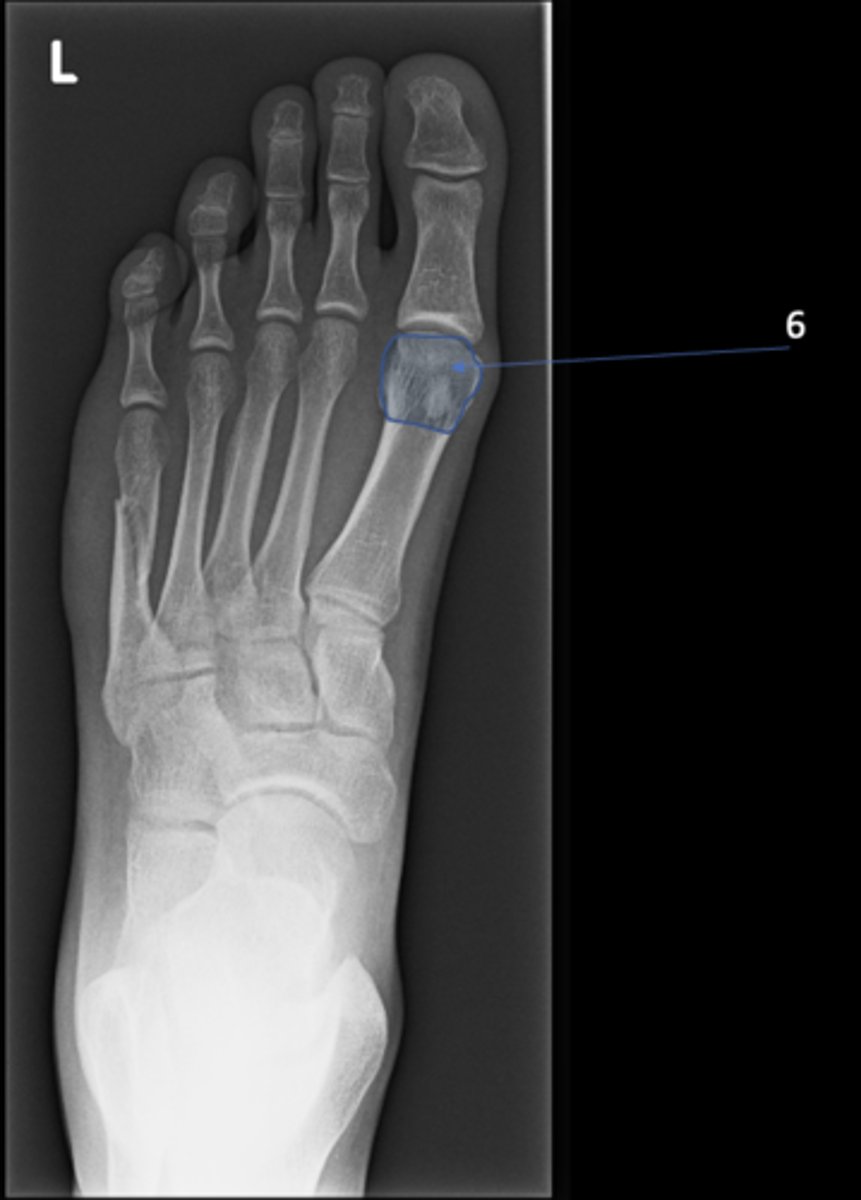

New cards

Left inferior pubic ramus

ID 15

<p>ID 15</p>

15

S1 tubercle

ID 16

<p>ID 16</p>

16